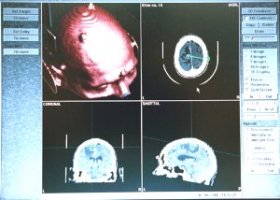

TECHNOLOGY IN NEUROSURGERYThe technology used in neurosurgery is changing all the time. The neurosurgeons of Neurosurgical Consultants, Inc., Drs. Freed, Friedberg, and Gieger attend continuing educational courses on a regular basis and bring these changes into their practice of Neurosurgery. The use of magnification and special lighting during surgery is an "everyday" routine for these neurosurgeons. The operating microscope used by Neurosurgical Consultants is a late model microscope offering excellent optics, lighting and zoom magnification from 6X to 12X. The controls on the microscope are all motorized for precision and ease of use. Stereotactic surgery is minimally invasive surgery with extreme accuracy. It is the computerized link between a CT Scan or MRI Scan to the equipment used in the operating room. With a stereotactic technique, neurosurgeons can precisely place a needle into a very small lesion or tumor with an accuracy of one millimeter. Dr. Freed has been performing stereotactic minimally invasive brain surgery since its beginning in the early 1980's. Drs. Friedberg and Gieger had extensive training in this technology prior to joining the practice in July 1999 and December 2008 respectively . Neuronavigation,, is the application of 3D views of the patient's brain or spinal cord that are linked by computer to the instruments used during surgery. It includes stereotactic surgery. The acquisition of a BrainLab Neuronavigation System at the Steward Norwood Hospital has allowed the neurosurgeons of Neurosurgical Consultants, Inc., to stay in the forefront of this rapidly changing field. Spinal Fusions are not new to neurosurgeons. However, the development of metal (usually light weight Titanium) plates, rods and screws allow neurosurgeons to "lock" the bones in place. This allows for quicker healing. We now have in our armamentarium devices that maintain the height of a disc space after removal of the disc. These interspace "cages" come in different shapes and sizes. Some are made of Titanium, others come from donor bone. The uses of these devices and grafts has allowed for much shorter and easier lumbar fusion operations. Patients have less pain, ambulate sooner and are usually able to leave the hospital on the second postoperative day. Some techniques incorporate Neuronavigation to place the devices with greater accuracy and less risk than ever before. Makers of these devices include Medtronic and Globus Medical, and others. Pain control often falls into the discipline of Neurosurgery. There are now numerous Implantable devices used to control chronic pain. These include implantable pumps that constantly deliver medication into the spine and stimulators with electrodes that lay over the spinal cord. Both of theses implants block the sensation of pain before it gets to the brain. The doctors of Neurosurgical Consultants, Inc. are well versed in the latest pain implant technology. There are several vendors for these implants. Our most common supplier is Medtronic. Vertebral Compression Fractures are common problems for people 60 years and older. These fractures are very painful and often debilitating in this age group. Because these patients often have osteoporosis the fractures do not always heal well. The deformity in the bone can progress and lead to breathing and walking problems. In the past, the surgical treatment of spinal compression fractures involved long complicated operations with implantation of metal hardware. For a variety of reasons, many of these patients could not tolerate or benefit from this extensive surgery. Also, the recovery was long and difficult. We can now stabilize these fractures with a minimally invasive technique called Kyphoplasty. Through one or two small (5 mm) incision(s) on the back, a catheter with a balloon, called "KyphX Inflatable Bone Tamp", is passed into the fractured vertebrae under x-ray guidance. After expanding the balloon (and the bone) plastic cement is injected into the cavity to stabilize the bone and relieve pain. Patients are often ambulatory the next day and out of the hospital in one to two days. The balloon devise is manufactured by Kyphon. For more information, please click on: "Evaluation and Treatment of Vertebral Compression Fracture." Neurosurgeons often use CT Scans to make urgent diagnoses and plan treatments for patients in the emergency room and at other times. "Teleradiology" is the technology that allows physicians to see CT Scans, MRI Scans and other imaging studies from a remote location. Our office computer is available to view such images from Caritas Norwood and Caritas Good Samaritan Hospitals. During off hours, this technology is also available to the "on call" physician. Soon after an emergency CT Scan has been completed and we are notified, the neurosurgeon can access the scan, review the images and advise the treating physicians and nurses at the hospital on the best treatments for these often critically ill patients. If surgery is indicated, the preparation of the patient and the operating room gets underway, even before the neurosurgeon arrives at the hospital. This time saving can make a big difference in a patient's outcome. Electronic Medical Record (EMR) keeping systems are now present in many doctors’ offices. They provide instant access to the all the parts of a patient's "chart." No longer must the paper chart be found before a question can be answered or prescription refilled. In addition to the obvious improved efficiency, patient privacy is maintained better than ever before. Neurosurgical Consultants, Inc. was one of the first practices in its coverage area to implement an EMR, in 2002. The electronic medical record solution used by Neurosurgical Consultants, Inc. is provided byAllMeds and meets all HIPAA requirements for privacy. ![]() ![]() |